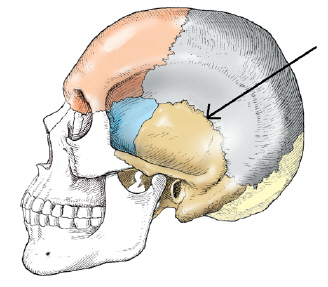

the superior aspect of the sphenoid bone contains a deep depression that contains the

pituitary gland

dorsum sellae